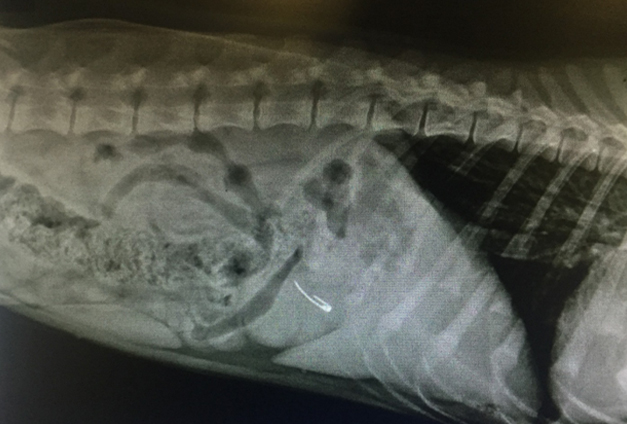

Во время приема отмечена болезненность при глубокой пальпации брюшной полости в области желудка. Ветеринарным врачом было принято решение о проведении рентгенологического исследования, в результате которого выявлено рентгеноконтрастное инородное тело (булавка) в проекции желудка (см. фото).

Было принято решение о проведении оперативного хирургического вмешательства. Была проведена предоперационная терапия и подготовка Сэма к операции. В ходе лапаротомии (хирургический доступ в брюшную полость) инородный предмет (булавка) был успешно извлечен из полости желудка (см. фото).